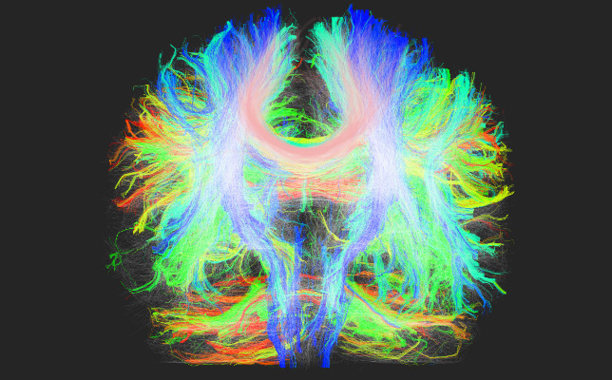

En este caso, usaron una modalidad de resonancia magnética llamada resonancia de difusión. Mediante un procedimiento denominado tractografía, pueden saber cómo se conectan entre sí diferentes áreas de interés del cerebro.

En esta caso, usaron una modalidad de resonancia magnética llamada resonancia de difusión, llamado tratografía

“Es algo así como elaborar un mapa de carreteras, pero la información que obtenemos no nos dice cuánto tráfico hay en esas carreteras, sino si son carreteras con mayor o menor capacidad, o si están en mejor o peor estado.

«Toda esta información se agrupa en algo llamado conectoma, que es una cantidad enorme de información que se puede explotar después”, precisan.